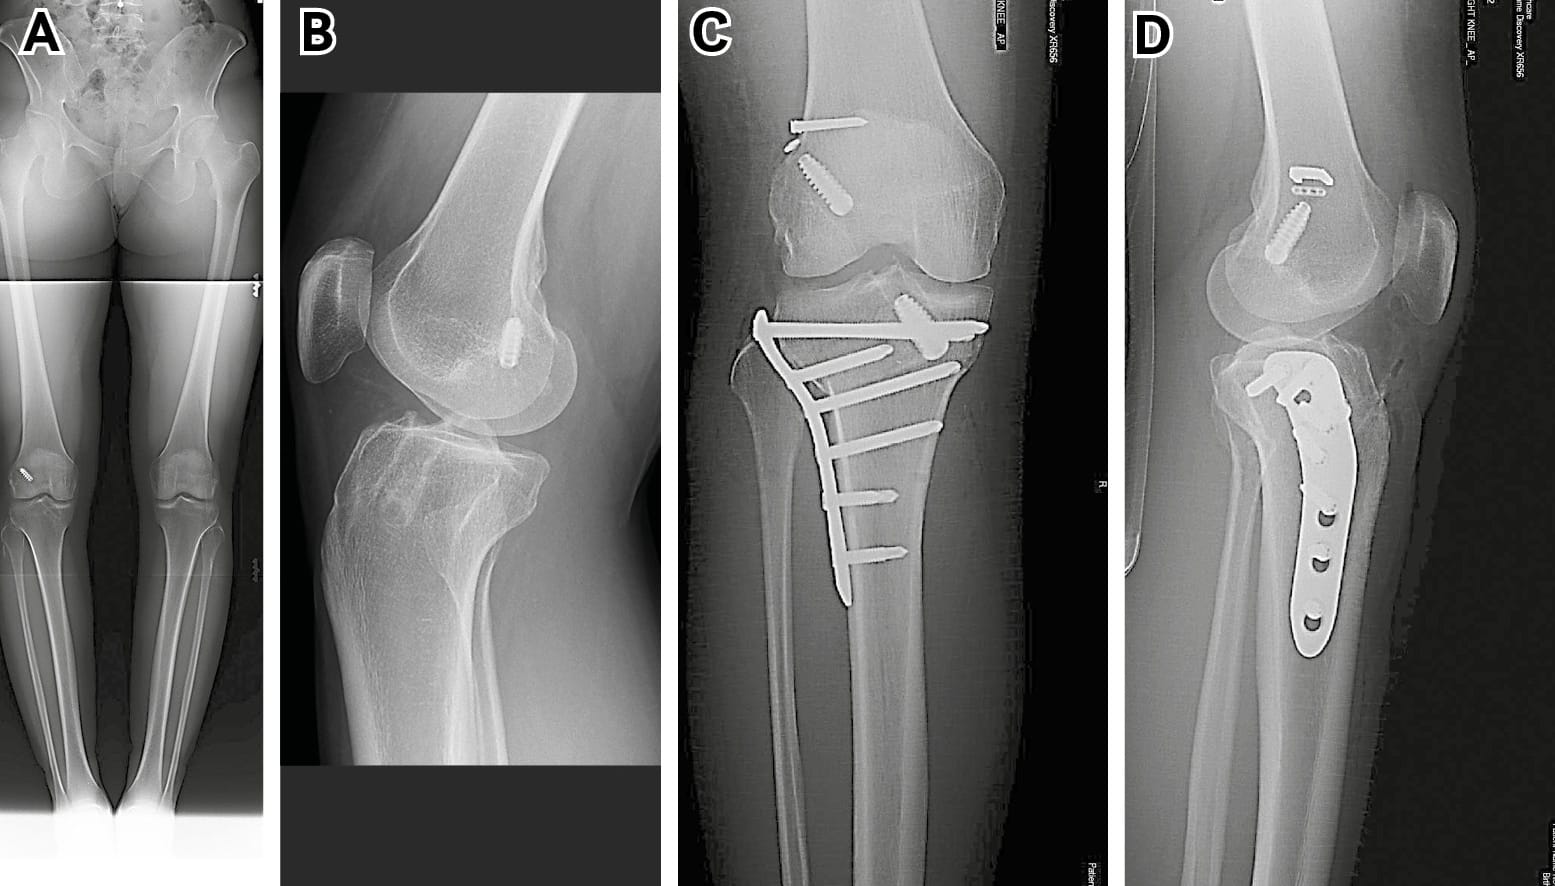

A full series of plain radiographs are important. These should include long leg alignment films and good lateral x-rays to assess the tibial slope (figure 1). There is a tendency for the eye to go straight to any metal implants but actually what is important is the position of the tunnel relative to these. The tunnel may be anterior, posterior, medial or lateral (or a combination) to the metal implant. It is for this reason it is rarely wise to comment on a previous surgeon’s tunnel position based on plain x-rays alone. The impression of a poorly placed tunnel may be completely incorrect (figure 2). This is particularly the case with grafts with bone blocks as the screw is normally adjacent to the bone block and therefore the soft tissue element of the graft may be some way away from the screws. Casual comments by a surgeon can lead to unfair lawsuits that could have been avoided.

CT scanning is much more valuable and as well as sagittal and coronal reformatting, a three-dimensional imaging can be provided. A CT based classification for femoral tunnel location has been described by Magnussen et al [3] Magnussen RA, Debieux P, Benjamin B, Lustig S, Demey, Servien E, Neyret P. A CT-based classification of prior ACL femoral tunnel location for planning revision ACL surgery. Knee Surg. Sports Traumatol. Arthroscopy. 2012; 20: 1298-1306. The three-dimensional reformatting capacity can be especially useful.